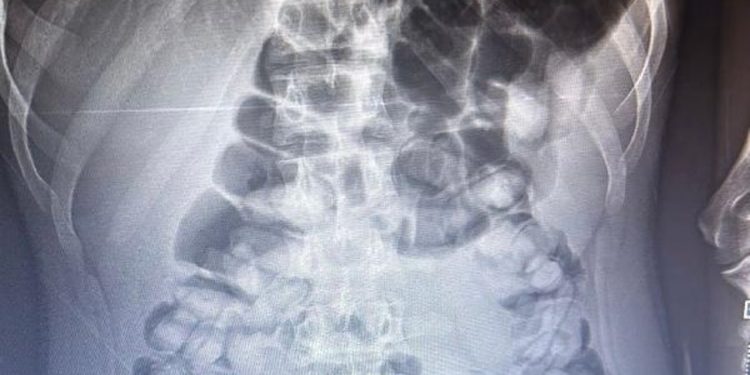

وبعد تفتيش حافلة ركاب تم نقل أحد الركاب المشتبه فيهم إلى المستشفى، وهناك تم الكشف عن وجود مخدرات في معدة الراكب من خلال إجراء فحص الأشعة السينية له.

وتم إزالة 1 كيلو و134 جرامًا من صمغ أفيون بشكل طبيعي من معدة الراكب بعد إعطاءه الدواء اللازم.